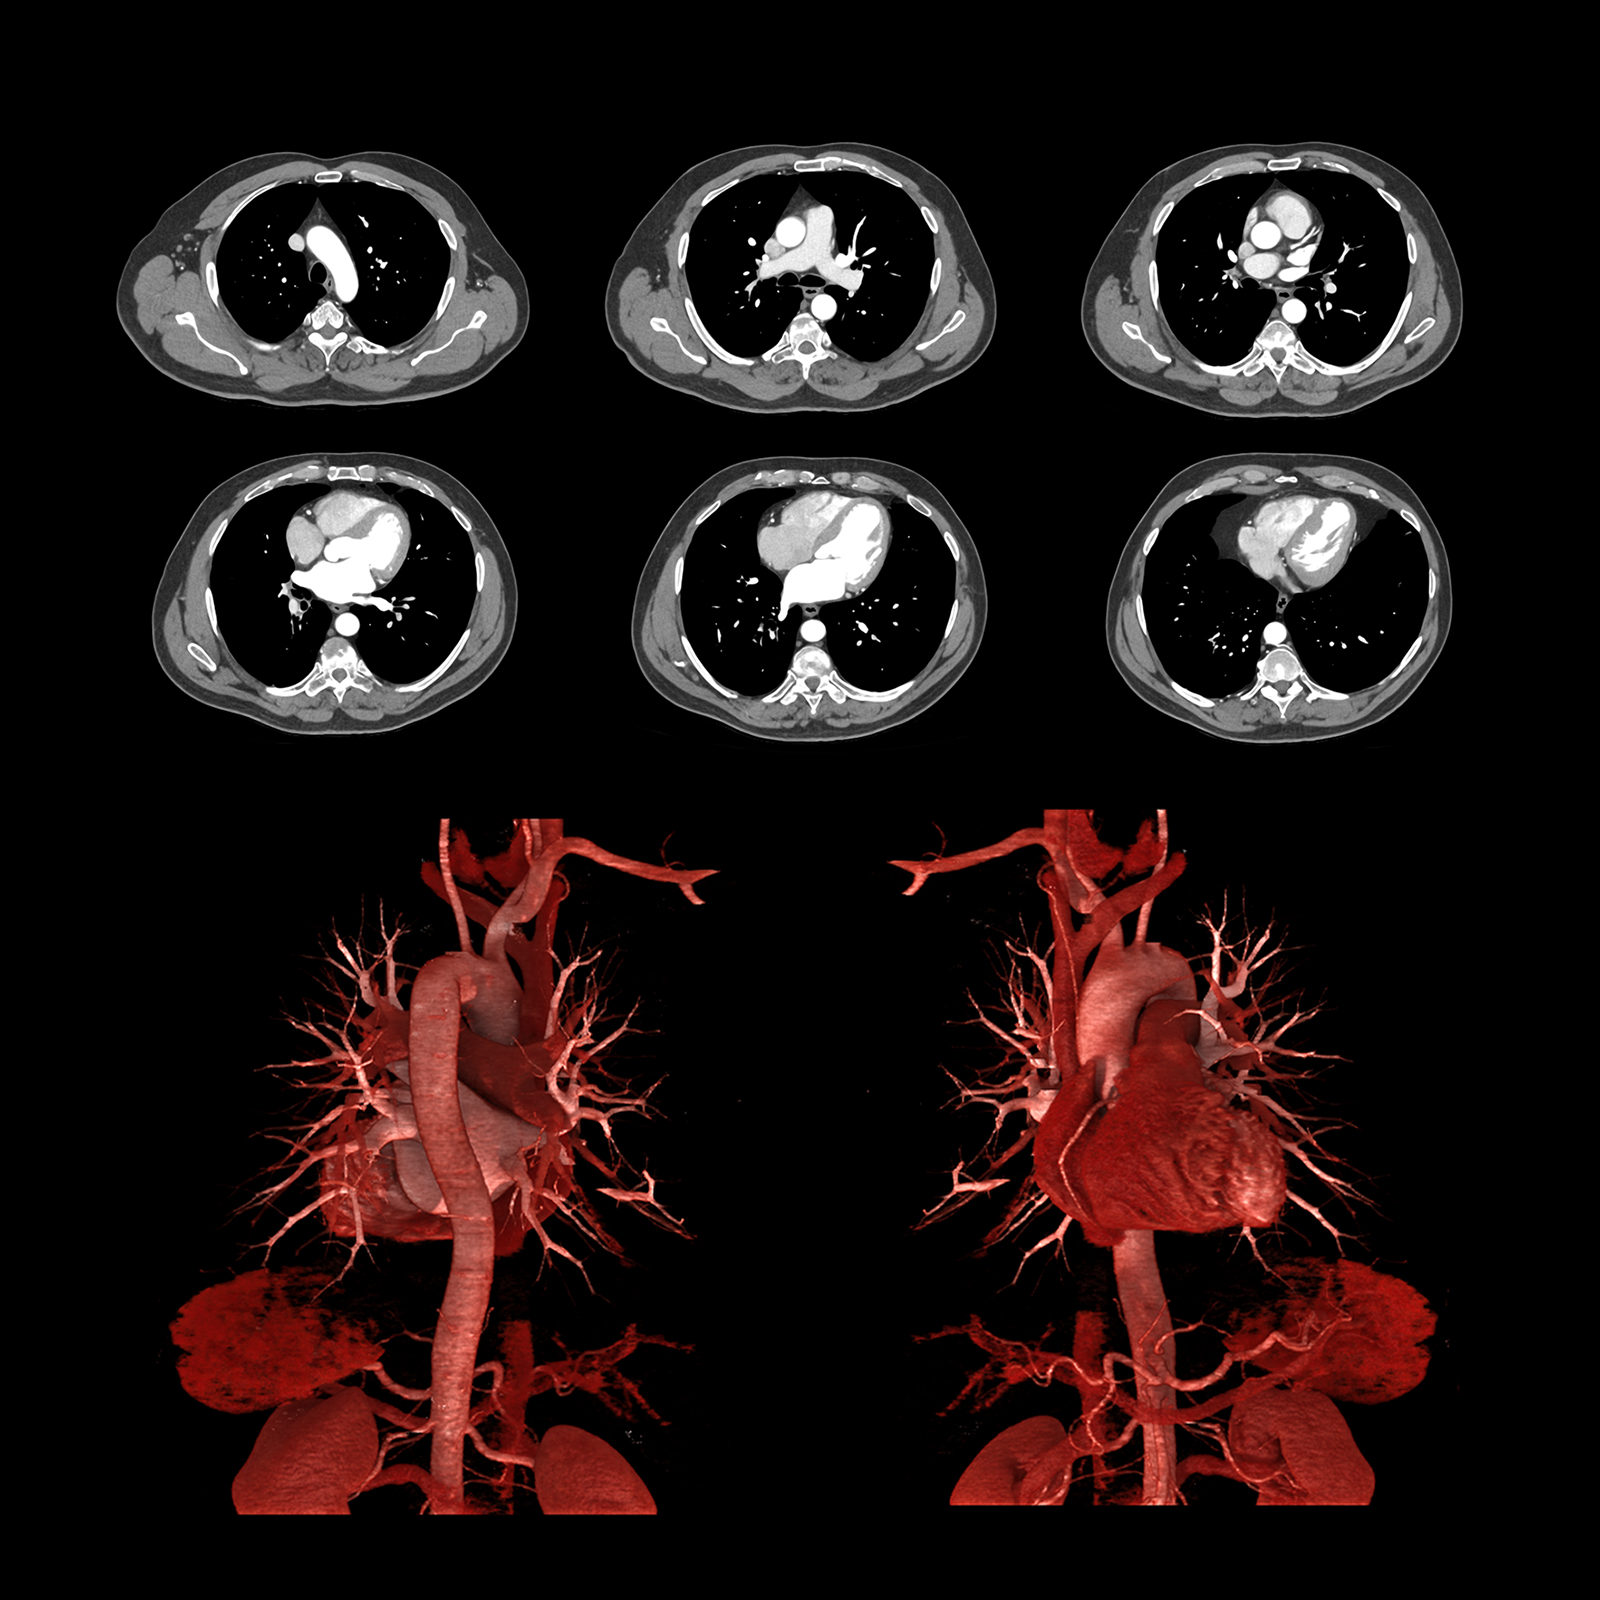

Преодолейте проблемы визуализации коронарных артерий в стентах и сильно кальцифицированных сосудах, объединив мощность однократного сердечного ритма и улучшенную резкость изображения с помощью искусственного интеллекта с PIQE. Реконструкция глубокого обучения со сверхвысоким разрешением PIQE обеспечивает четкие изображения сердца без ущерба для шума, временного разрешения или дозы.

Precise IQ Engine (PIQE)

PIQE обеспечивает улучшенное пространственное разрешение и снижение шума на 45%* для улучшения визуализации в стенте с четким изображением просвета сосуда для оценки неоинтимальной гиперплазии и рестеноза в стенте. Высокая контрастность по сравнению с шумовыми свойствами исследований PIQE также обеспечивает лучшую оценку в сильно кальцифицированных коронарных артериях без потери низкоконтрастной обнаруживаемости* — и эти преимущества обеспечиваются без дополнительной дозы.

Надежные для всех пациентов исследования One beat CTA с PIQE предлагают:

- более четкие анатомические детали,

- уменьшение засветов кальция,

- без дополнительной дозы,

- изофазная однородность.

*по сравнению с AIDR 3D